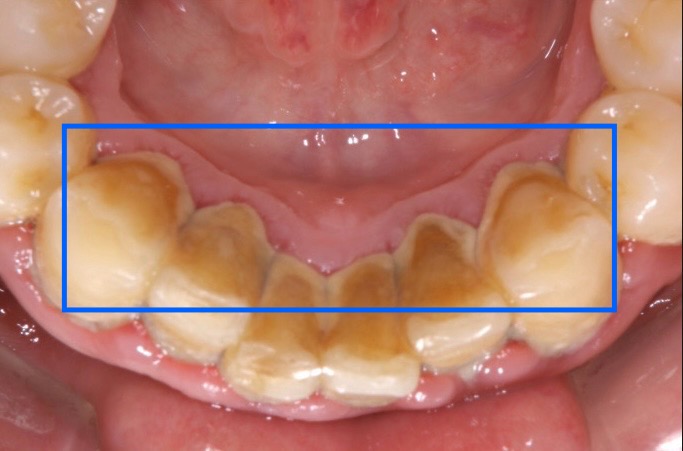

歯肉縁上歯石(しにくえんじょうしせき)・・歯茎より上にできる歯石

歯肉縁下歯石(しにくえんかしせき)・・歯茎より下にできる歯石

歯肉縁上歯石の特徴

・黄白色または灰白色

・唾液によって石灰化する

・縁下歯石より柔らかく除去しやすい

・歯肉炎の原因になる

歯肉縁下歯石の特徴

歯と歯肉の間の溝(歯周ポケット)に面した歯根面に付着した歯石です。歯周ポケットからの滲出液や血液により黒褐色になります。